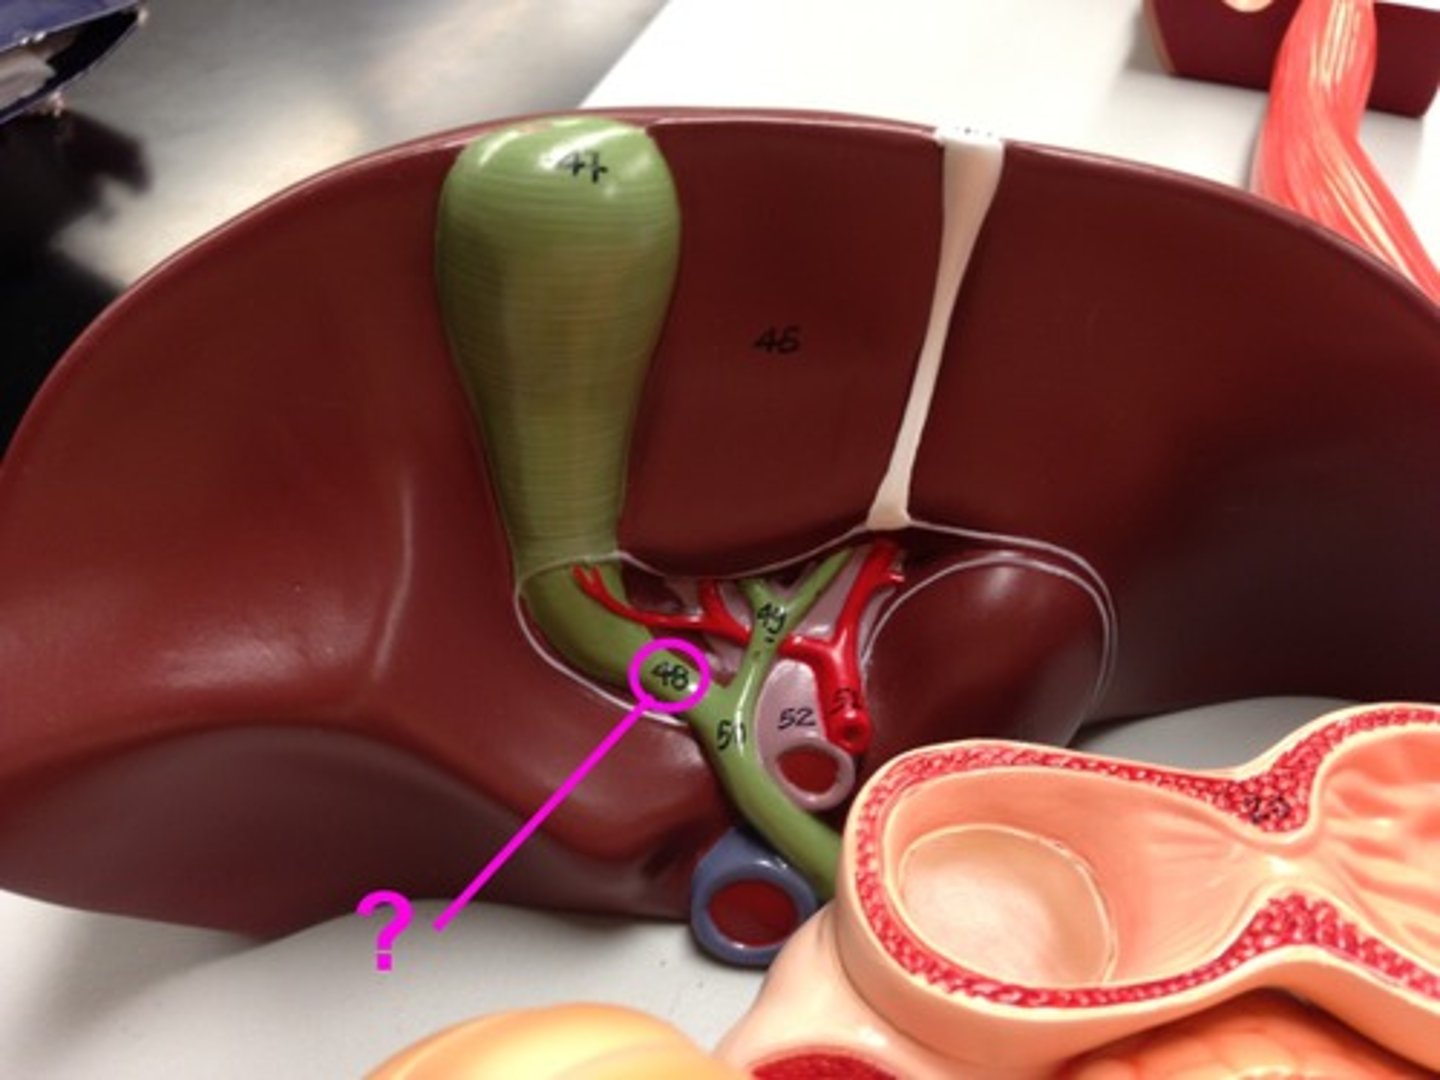

hepatoduodenal ligament

portal triad

what is in this structure

porta hepatis

where the blood and lymph vessels, bile ducts, and nerves enter and leave the liver

common bile duct

common hepatic duct

cystic duct

hepatic portal vein